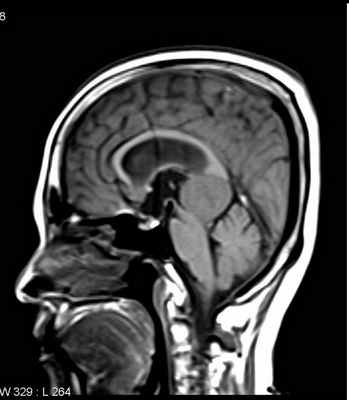

МРТ головного мозга. Нейрофиброматоз тип II. Менингиома нижнего сагиттального синуса. Аксиальная и сагиттальная Т1-зависимые МРТ с контрастированием.

Тот же пациент. Внутрижелудочковая менингиома. Аксиальная Т2-зависимая МРТ, поперечная и сагиттальная Т1-зависимые МРТ с контрастированием.